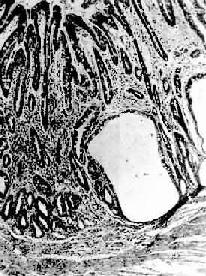

一、胃炎胃炎(gastritis)是胃粘膜的炎性变化,是一种常见病,可分为急性胃炎和慢性胃炎。慢性胃炎可由急性胃炎反复发作迁延而来,但多数因其他全身性因素及胆汁反流至胃内引起。近年发现,从慢性胃炎患者胃粘膜中分离出一种螺旋状弯曲杆菌,命名为弯曲样细菌(campylobacter like organisms,CLO),经研究证明本菌与胃炎之间关系密切,该菌不仅适应胃内高酸环境,还可降解胃粘膜表面被覆粘液使其失去保护作用,故被认为是慢性胃炎的一种病原因素。 (一)急性胃炎 急性胃炎(acute gastritis)常见者有4种: 1.急性卡他性胃炎(acute catarrhal gastritis)多因暴饮暴食引起,亦称刺激性胃炎(irritation gastritis)。胃粘膜充血、水肿有时可见粘膜糜烂。 2.腐蚀性胃炎(corrosive gastritis)由咽下高浓度酸、碱或腐蚀性化学剂引起。病变多较严重,胃粘膜出现坏死、软化溶解。 3.急性蜂窝织炎性胃炎(acute phlegmonous gastritis)少见,是一种弥漫性化脓性炎,病情较重。可由金黄色葡萄球菌、链球菌或大肠杆菌等化脓菌经血行感染(败血症)或直接感染(创伤)侵入胃壁引起。 4.急性出血性胃炎(acute hemorrhagic gastritis)主要表现为胃粘膜急性出血合并轻度坏死。本病发生与服用某些药物(如水杨酸制剂)、过量应用肾上腺皮质激素及过度饮酒有关。 (二)慢性胃炎 慢性胃炎(chronic gastritis)是一种常见病。一般分为表浅性及萎缩性二种。 1.慢性表浅性胃炎(chronic superficial gastritis)本病在胃窦部最为常见,为常见的胃粘膜疾患之一,纤维胃镜检出率高达20%~40%。 【病变】 肉眼观,病变多为多灶性或弥漫性,病变胃粘膜充血、水肿,有时并伴有点状出血或糜烂。镜下,可见炎性病变主要限于粘膜浅层,呈弥漫性或灶状分布。浸润的炎性细胞主要是淋巴细胞和浆细胞,有时可见少量嗜酸性粒细胞及中性粒细胞。此外可见粘膜浅层出现水肿、小出血点或表浅上皮坏死脱落。 2.慢性萎缩性胃炎(chronic atrophic gastritis)本病炎症改变并不明显,主要是胃粘膜的萎缩性变化。此时胃粘膜萎缩变薄,腺体减少或消失。临床上可有胃内游离盐酸减少或缺乏、消化不良,上腹不适或钝痛、贫血等症状。 【病因和分型】 现今将萎缩性胃炎分为A、B二型。已知A型发病与免疫因素关系密切,病人血中可找到抗胃壁细胞微粒体的自身抗体。病变在胃体部,并有维生素B12吸收障碍,常合并恶性贫血,可找到抗内因子抗体。B型的发病则与自身免疫无关,同时并不伴有恶性贫血也找不出自身抗体。其病因可能与吸烟、酗酒或滥用水杨酸类药物(如APC)等有关。B型亦称单纯性萎缩性胃炎,在我国较为多见。其病变部位在胃窦部,有的并可能发生癌变。两型萎缩性胃炎的胃粘膜病变基本一致。 【病变】 胃粘膜薄而平滑,皱襞变浅,有的几乎消失。粘膜表面呈细颗粒状。胃镜检查,可有3个特点:①正常胃粘膜的橘红色色泽消失,代之以灰色;②萎缩的胃粘膜明显变薄,与周围的正常胃粘膜界限明显;③萎缩处因粘膜变薄,粘膜下血管分支清晰可见。 镜下,病变区腺上皮萎缩,腺体变小并可有囊性扩张,常出现上皮化生(假幽门腺化生及肠上皮化生)。在粘膜固有层有不同程度的淋巴细胞和浆细胞浸润。在胃体和胃底部病变区,主要呈现壁细胞消失,其次是主细胞消失和粘液分泌细胞化生。后者称为幽门腺或假幽门腺化生。电镜观察,壁细胞除数量减少外,可见细胞内自噬泡增多,内质网扩张,高尔基器减少,线粒体肿胀,表面微绒毛消失。内质网、高尔基器和微绒毛是壁细胞的功能部分,其减少或消失反映了细胞泌酸功能的低下或消失。在幽门窦病变区,主要改变为幽门腺呈不同程度的萎缩、消失(图10-3)并常有肠上皮化生。胃粘膜表层上皮细胞生长,可形成绒毛样突起,增生的上皮中出现分泌粘液的杯状细胞(图10-4)、具有刷状缘的吸收上皮细胞和Paneth细胞时其形态结构与小肠粘膜相似,故称为肠上皮化生。现知肠上皮化生的胃粘膜易诱发胃癌,多为息肉样腺癌。

图10-3 慢性萎缩性胃炎 幽门腺大部分萎缩消失,胃小凹延长,有潴留性小囊形成,腺上皮中杂有不少杯状细胞(肠上皮化生),固有膜内有不少慢性炎性细胞浸润(Ⅱ74-4950) 胃粘膜的肠上皮化生分为小肠型及大肠型二种,二型中又分别分出完全肠上皮化生与不全肠上皮化生(图10-4)。小肠型与大肠型肠上皮化生可从光镜的腺体形态及粘液组化反应加以鉴别。Teglbjaerg曾报告含氧乙酰化唾液酸粘液者为大肠型化生,该粘液反应阴性者为小肠型化生。多数研究指出大肠型化生与肠型胃癌并存者较多,特别是不全大肠型肠上皮化生在癌旁组织中明显增多,其DNA含量及CEA的检出率均明显增加。但肠上皮化生究竟是否属于癌前病变迄今尚无定论。